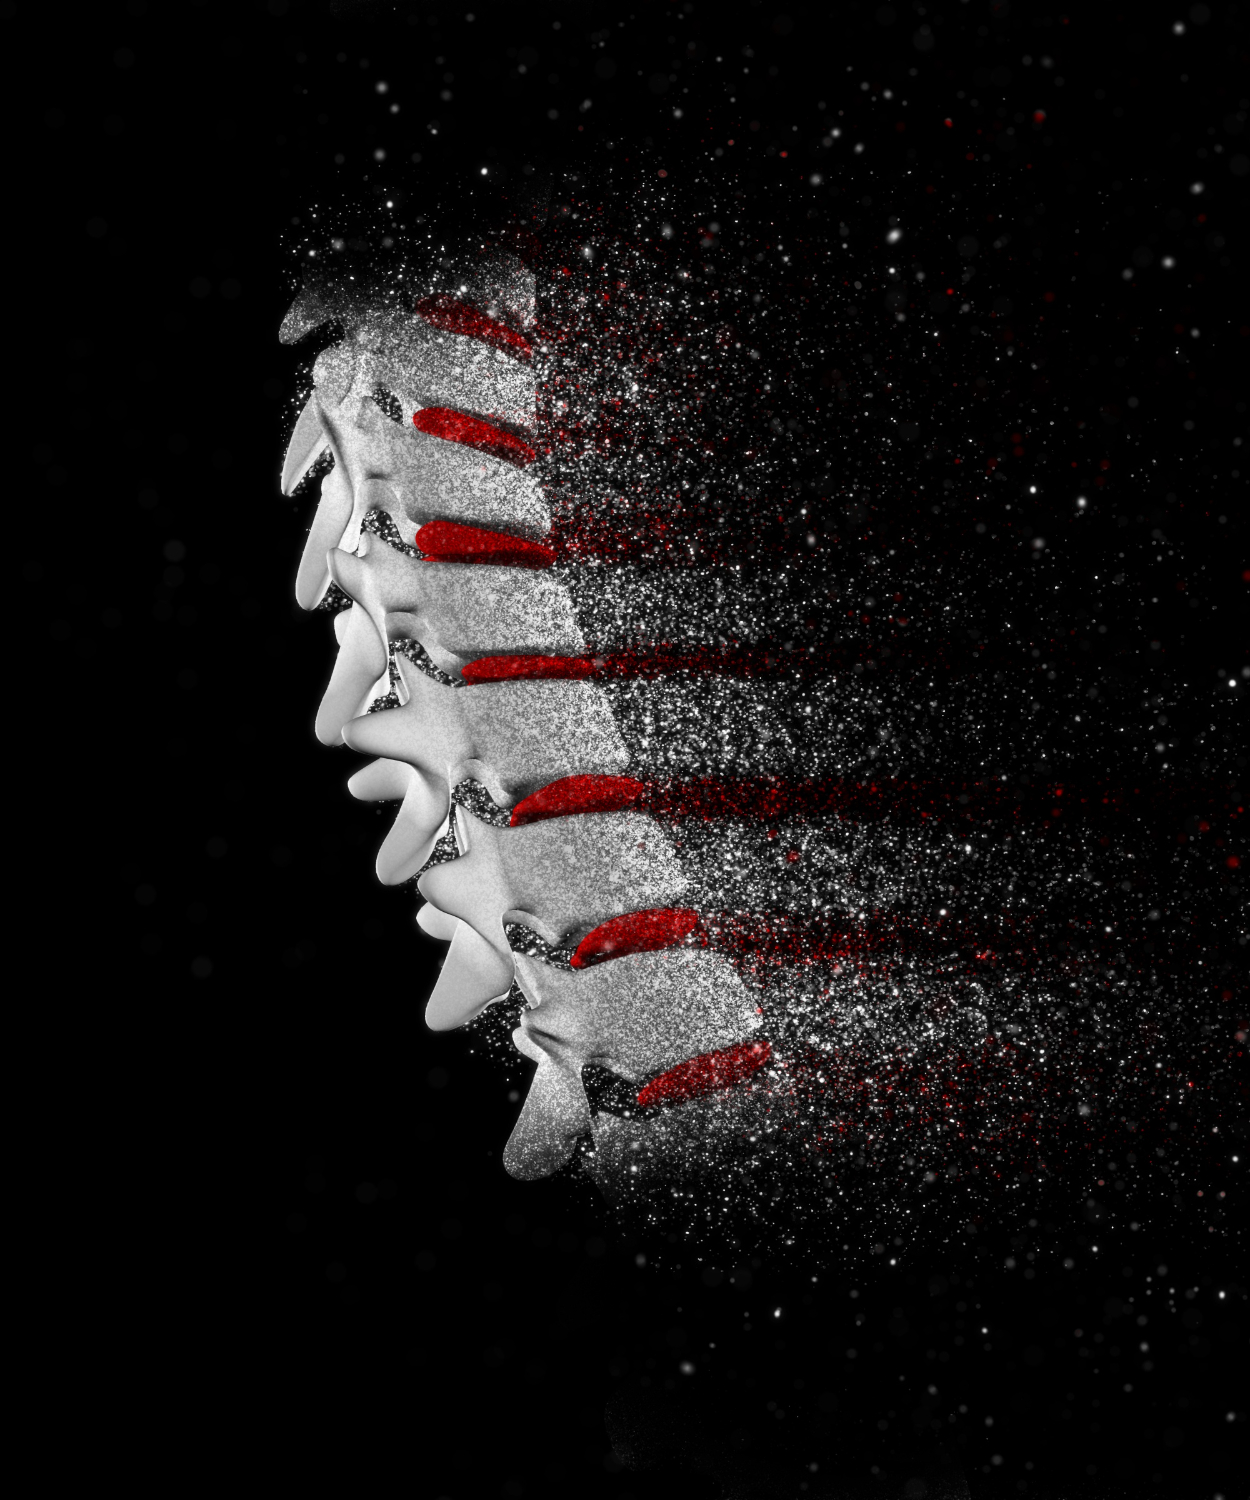

coluna vertebral

Diagnóstico e tratamento avançado para a coluna vertebral

A coluna vertebral é a estrutura central do corpo humano, responsável por sustentar o tronco, proteger a medula espinhal e garantir mobilidade e equilíbrio. Problemas na coluna, como hérnias de disco, escoliose e estenoses, podem causar dor, limitação de movimentos e impactar a qualidade de vida. Na Clínica N3, contamos com especialistas em neurologia e neurocirurgia preparados para diagnosticar, tratar e acompanhar doenças da coluna, oferecendo cuidado personalizado e tecnologia avançada para a recuperação e o bem-estar dos pacientes.

Tratamento avançado para doenças da coluna.

A coluna vertebral é a principal estrutura de sustentação do corpo humano, protegendo a medula espinhal e permitindo movimentos essenciais para o dia a dia. Alterações nessa região, como hérnias de disco, escoliose e estenoses, podem causar dor e comprometer a qualidade de vida. Na Clínica N3, oferecemos diagnóstico especializado e tratamento personalizado para doenças da coluna, unindo tecnologia avançada, experiência médica e cuidado humanizado para garantir mais saúde, mobilidade e bem-estar aos pacientes.